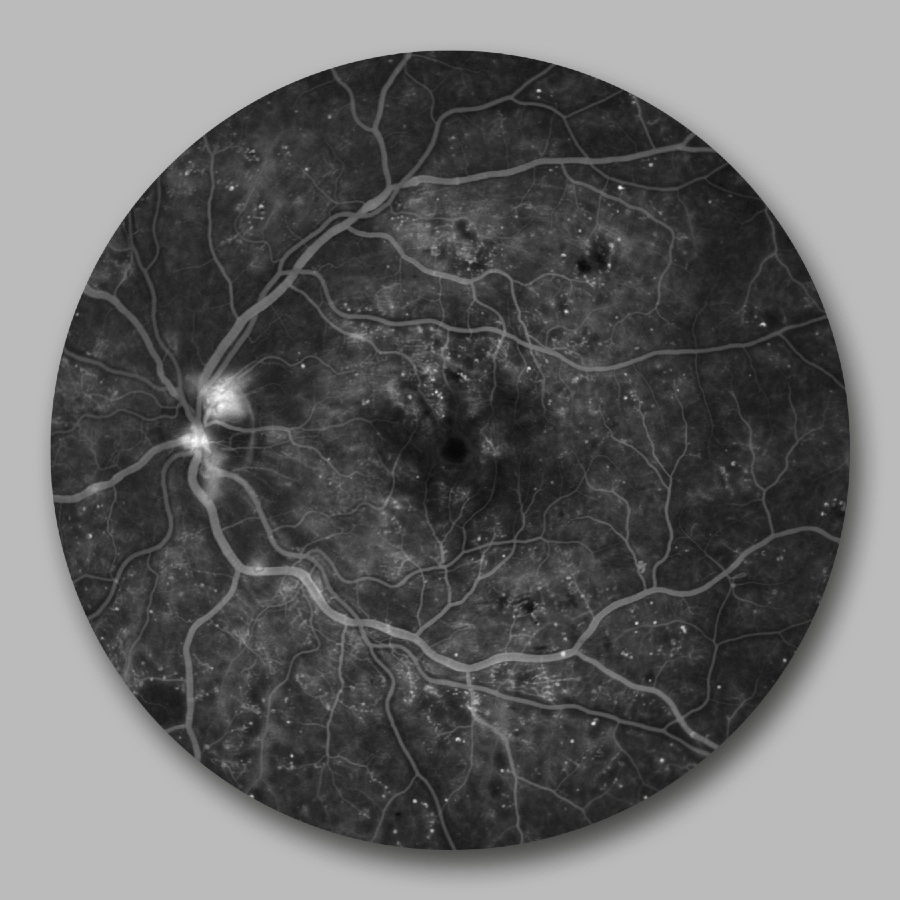

Optos scan: œdème maculaire diabétique

Angiographie en fluorescence: œdème maculaire diabétique